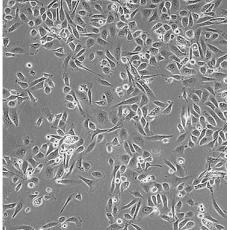

PC-3(PC 3)

中文名稱(chēng) 人前列腺癌細(xì)胞

組織來(lái)源 前列腺癌;骨髓轉(zhuǎn)移;男性

細(xì)胞種屬 Homo sapiens, human

生長(zhǎng)特性 adherent

培養(yǎng)基 Ham's F-12K+10% FBS+1% P/S

形態(tài)特征 epithelial

傳代方法 1:3-1:6

培養(yǎng)條件 Atmosphere: Air, 95%; CO2, 5%。Temperature: 37℃

細(xì)胞描述 PC-3源于一位62歲白人男性IV級(jí)前列腺腺癌患者的骨轉(zhuǎn)移灶;有低水平的酸性磷酸酶活性和5-α-睪酮還原酶活性。